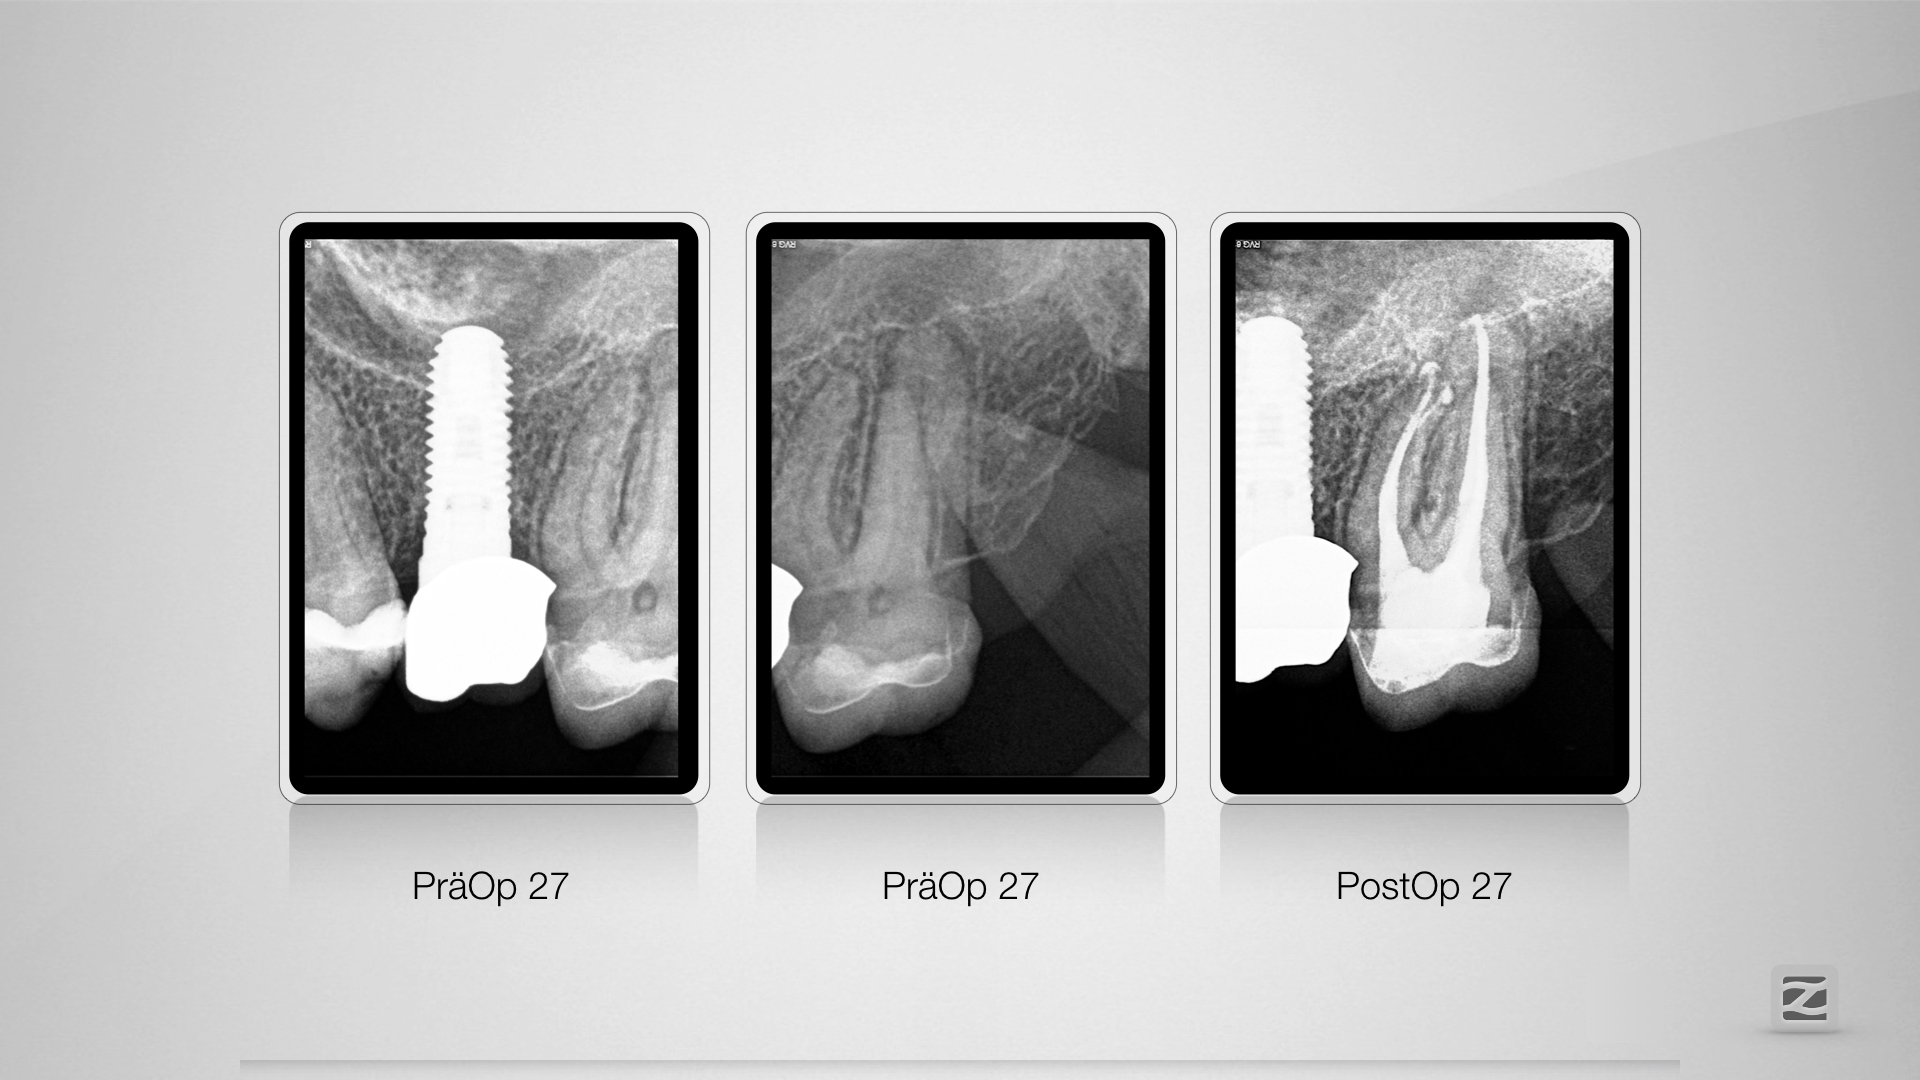

Tiefe apikale Aufgabelung